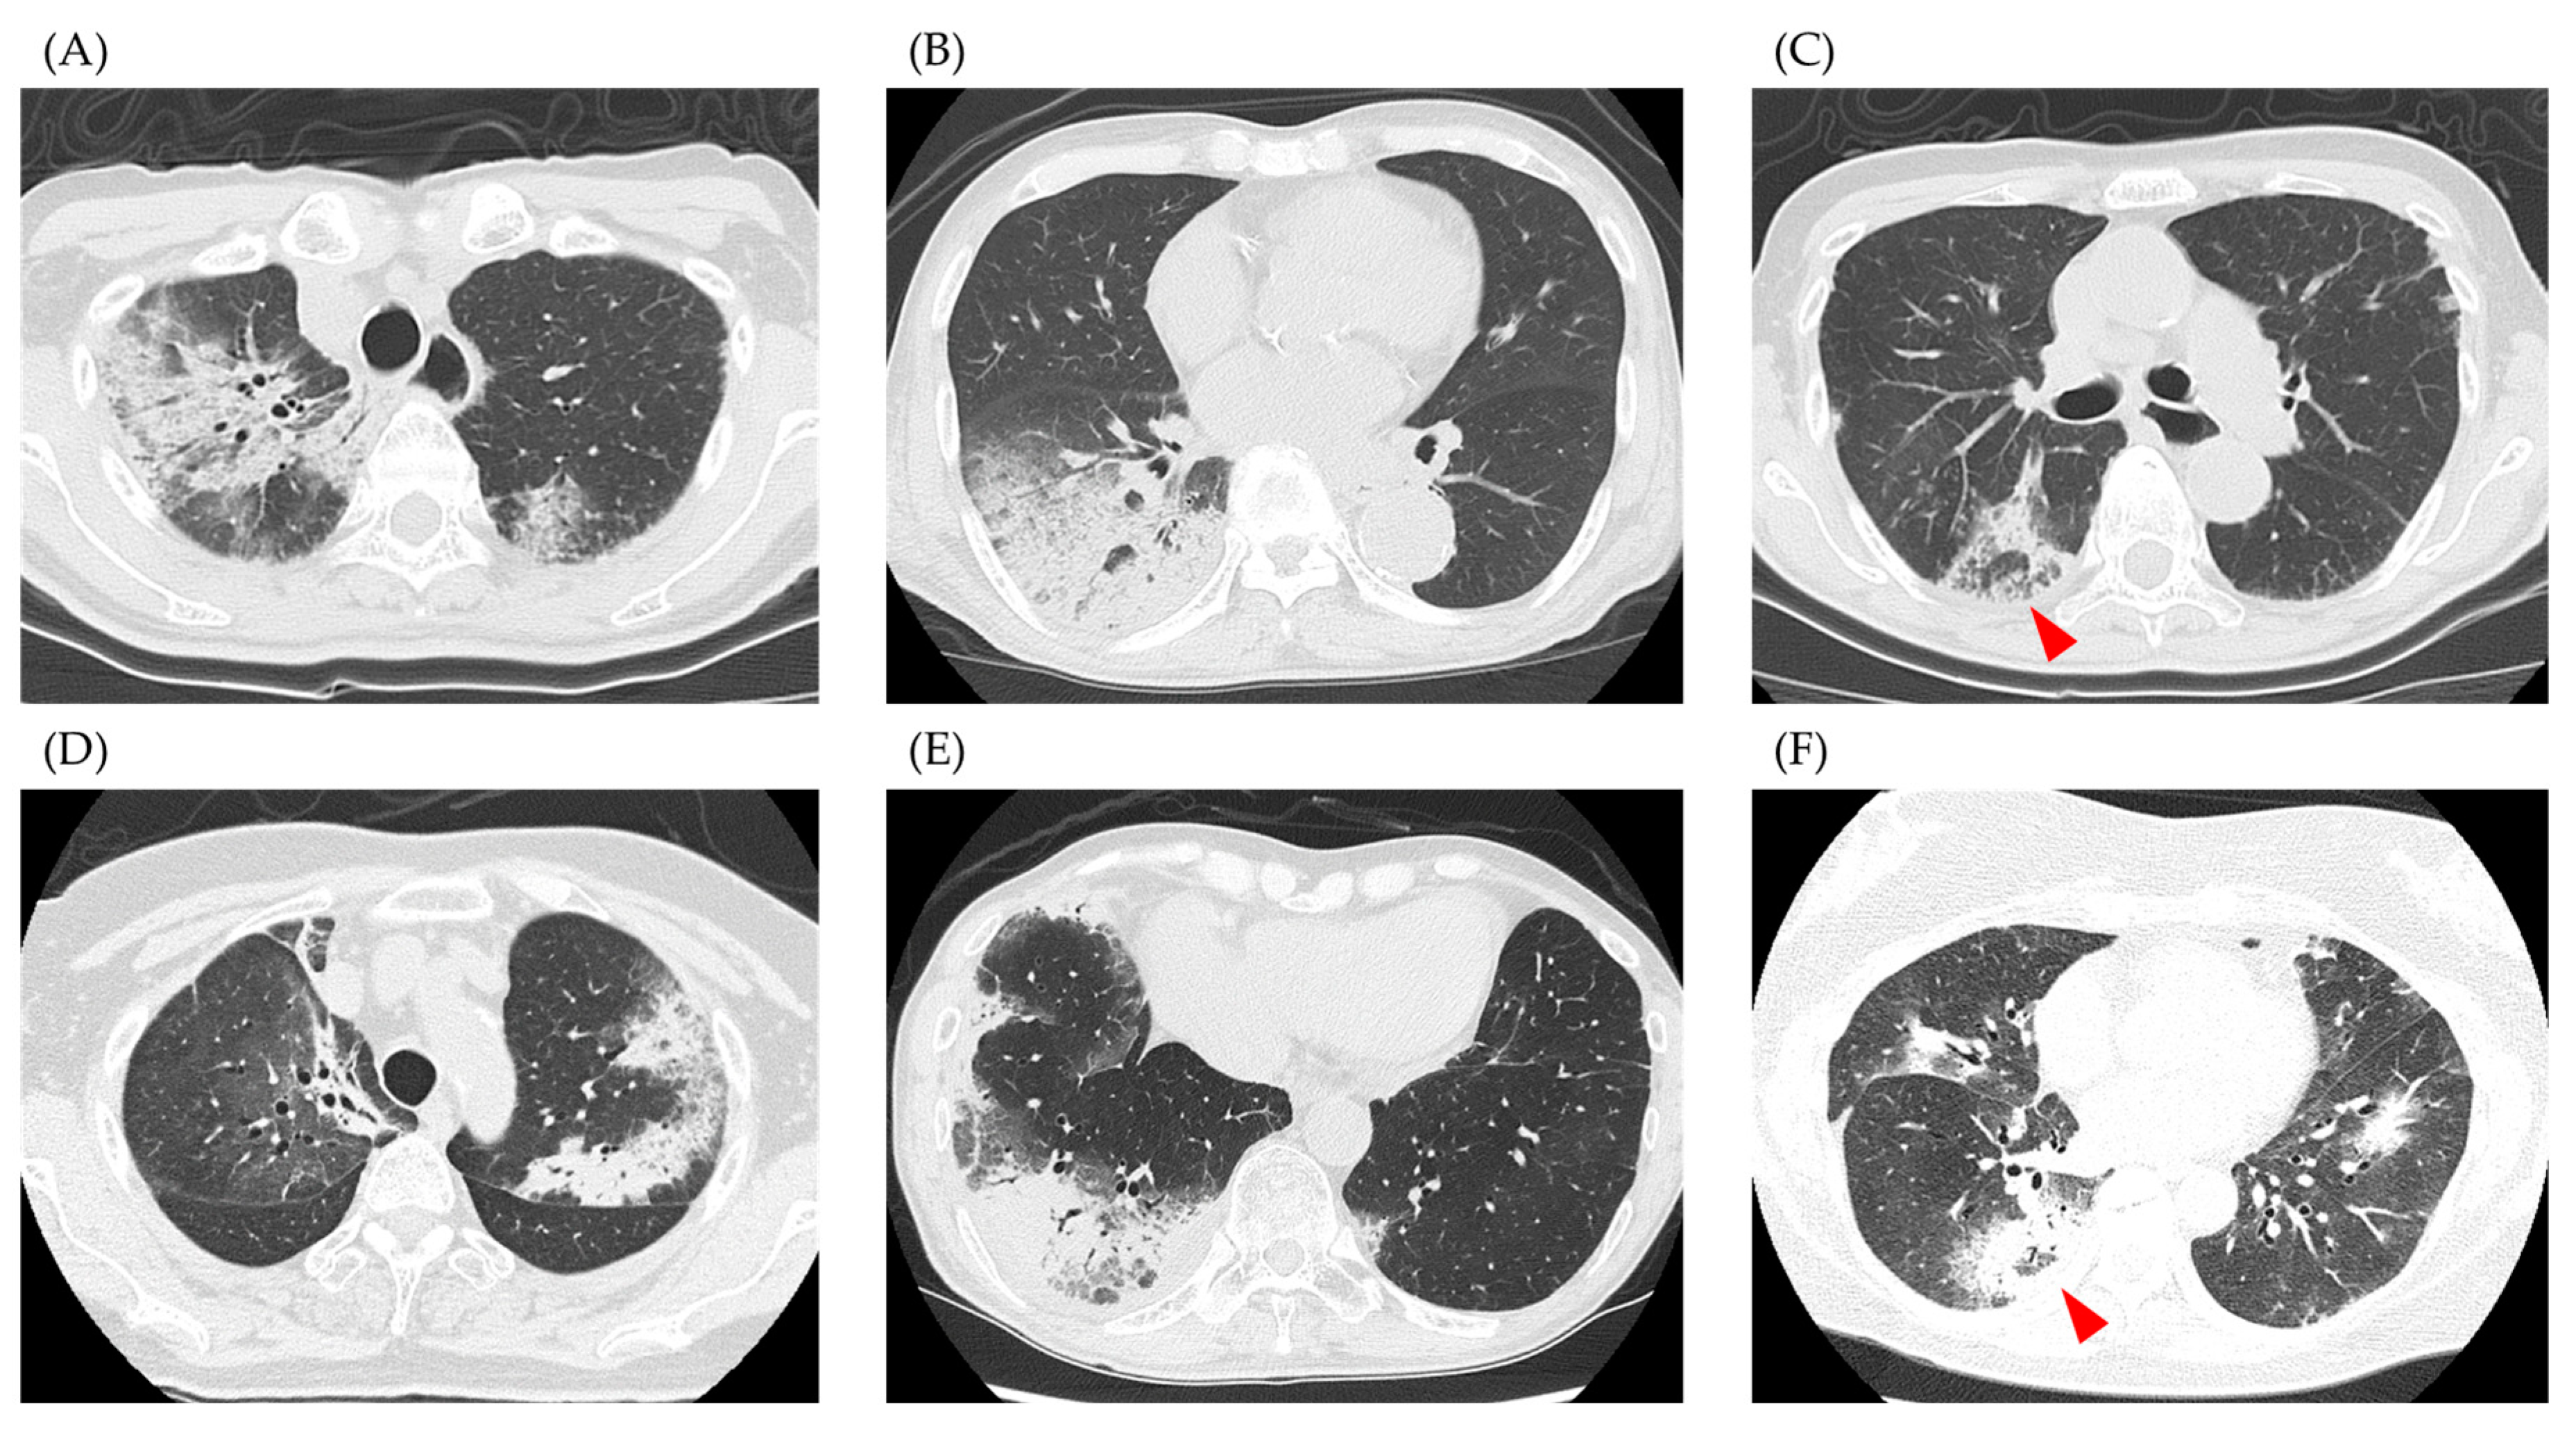

| Distribution | |||

| Bilateral | 7 (88) | 17 (77) | 1.00 |

| Peripheral dominance/Diffuse | 6/2 | 19/3 | 0.59 |

| Predominant pattern | |||

| Consolidation/Ground-glass opacity | 5/3 | 19/3 | 0.30 |

| Reversed halo sign | 1 (13) | 3 (14) | 1.00 |